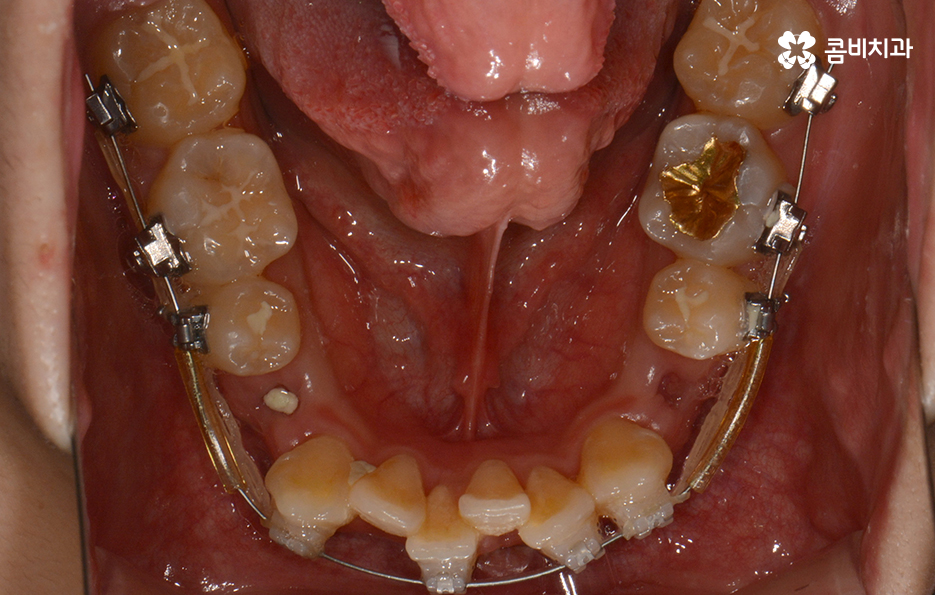

위 환자분의 케이스는 아랫니에 치아 2개를 발치하여

치아의 이동 공간을 확보하였고 발치교정이 진행될 때는

윗니와 아랫니 각각 2개씩 발치를 하는 경우가 많지만

위 사례는 치열, 교합 등을 고려할 때 아랫니 2개만

발치가 진행되었던 경우라고 볼 수 있어요.

왼쪽이 윗니이고 오른쪽이 아랫니인데 치열의 불규칙함이

심한 편이다 보니 평소 음식물이나 치석이 끼기 쉬운 환경이

되고 이러한 구강 환경이 지속된다면 충치와 잇몸질환의 발생률이 높아질 수 있어요.